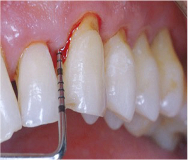

Fotos dos casos clínicos